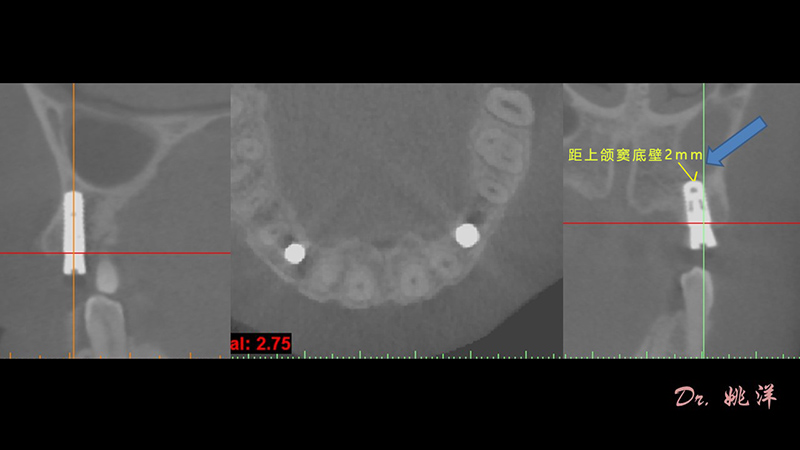

觀察患者CT,可看出患者有上頜竇粘膜囊腫,粘膜囊腫為竇內(nèi)腺體阻塞所致,視情況可有手術(shù)摘除和不予處理兩種方法,此次患者拒絕手術(shù)摘除,故需規(guī)避上頜竇位置。

術(shù)前設(shè)計(jì)

冠狀面視圖

矢狀面視圖

軸狀面視圖

三維視圖

根據(jù)患者CT顯示,使用種植導(dǎo)航軟件設(shè)術(shù)前手術(shù)方案??紤]到患者拒絕手術(shù)摘除上頜竇囊腫等因素,此次手術(shù)選用了Straumann骨水平4.10*8.0mm的植體,植體末端位點(diǎn)設(shè)計(jì)距上頜竇底壁2mm處的同時(shí)兼顧種植方向和修復(fù)間隙,來(lái)達(dá)到理想的效果。